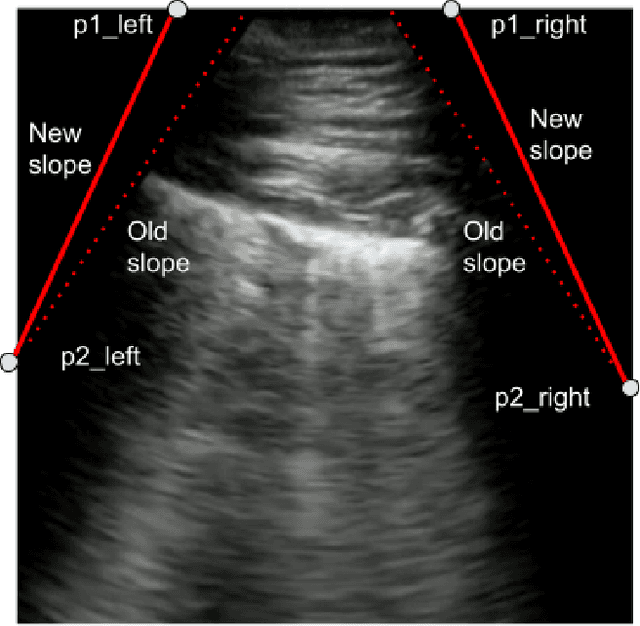

As the global population continues to face significant negative impact by the on-going COVID-19 pandemic, there has been an increasing usage of point-of-care ultrasound (POCUS) imaging as a low-cost and effective imaging modality of choice in the COVID-19 clinical workflow. A major barrier with widespread adoption of POCUS in the COVID-19 clinical workflow is the scarcity of expert clinicians that can interpret POCUS examinations, leading to considerable interest in deep learning-driven clinical decision support systems to tackle this challenge. A major challenge to building deep neural networks for COVID-19 screening using POCUS is the heterogeneity in the types of probes used to capture ultrasound images (e.g., convex vs. linear probes), which can lead to very different visual appearances. In this study, we explore the impact of leveraging extended linear-convex ultrasound augmentation learning on producing enhanced deep neural networks for COVID-19 assessment, where we conduct data augmentation on convex probe data alongside linear probe data that have been transformed to better resemble convex probe data. Experimental results using an efficient deep columnar anti-aliased convolutional neural network designed via a machined-driven design exploration strategy (which we name COVID-Net US-X) show that the proposed extended linear-convex ultrasound augmentation learning significantly increases performance, with a gain of 5.1% in test accuracy and 13.6% in AUC.